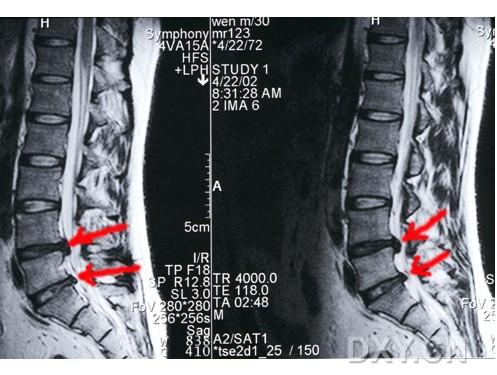

腰椎间盘突出症普及和自评 已有10人参与